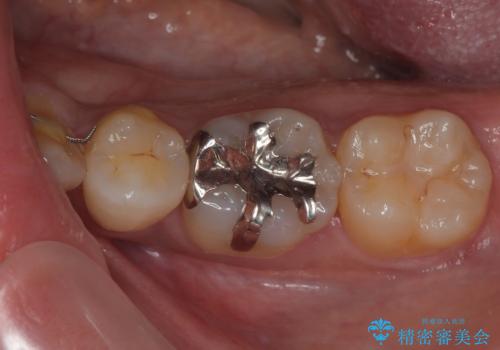

銀歯の下の虫歯を治したい オールセラミッククラウン・セラミックインレー修復